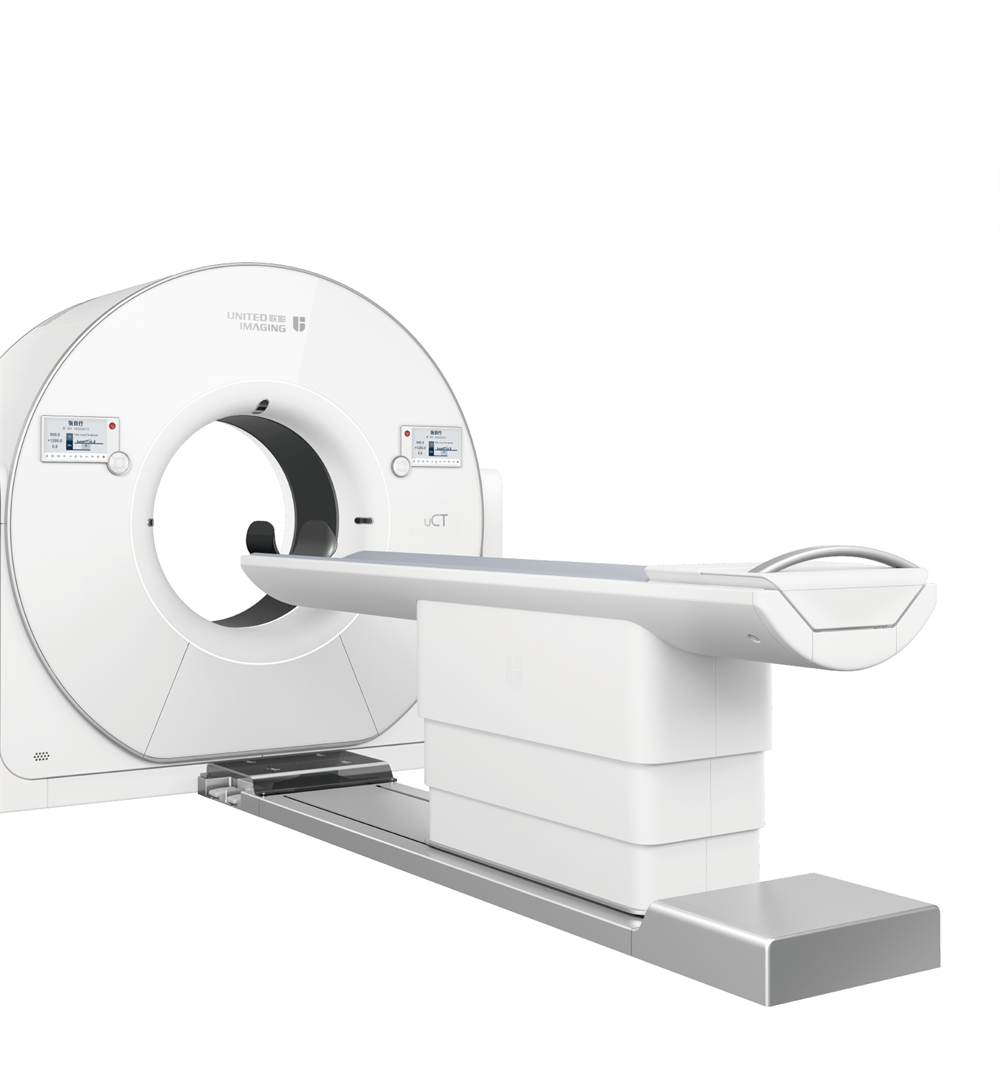

精准医疗,影像先行。10月1日,寿光和信医院新购置的“神探”影像设备640层CT和3.0T磁共振正式投入临床使用,这是全省为数不多的高端影像检查设备,将进一步改善群众就医体验,缩短就医时间,更好地造福广大民众的生命健康。

“高精尖”医疗设备,为诊疗步伐按下“加速键”,先进的医疗设备是医院高质量发展的硬核保障。寿光和信医院联影640层高端CT在临床诊断中发挥了重要作用,为大量患者提供了快速、高效、智能的检查服务,尤其在心脑血管疾病、急危重症等领域,提供了精准的影像信息。这种技术进步不仅提升了诊断的准确性,也为国家推动的胸痛中心、脑卒中中心、肿瘤中心和创伤中心的建设提供了有力支持。

联影640层CT是中国CT届的“天花板”,集当今CT领域的顶尖科技于一身,将各项临床应用发挥到极致,为患者带来精准、舒适、安全的CT检查新体验。建立了心血管、神经、肿瘤、呼吸系统、泌尿系统及骨科专业等疾病的成像和低剂量筛查领域全新标准,真正实现全方位成像,结合AI人工智能技术,提高疾病诊断率。

凭借先进硬件平台和独有的AI冠脉追焦技术,不管是对于严重心律不齐、房颤、房扑,还是超高心率等一般CT做不了的心脏检查的情况,联影640层CT都可以获得高清的成像效果,助力精准临床诊断。

采用液态金属轴承技术的超大热容量球管,结合独有的低千伏、低毫安成像模式,联影640层CT可实现肺部、冠脉等全身各部位大扫描通量、微辐射剂量的体检筛查。?

联影640层CT采用宽体采集,一次检查即可获得全脑平扫图像、动静脉造影图像和灌注图像,不仅可应用于急诊缺血性脑卒中的影像评估,还可助力脑血管畸形、脑动脉瘤等其他脑血管病的结构和功能评估。

针对胸痛、脑出血、外伤、急腹症等多种急诊检查场景,联影640层CT提供全速急诊方案,检查时间最短化,图像评估直观化,为生命争分夺秒。